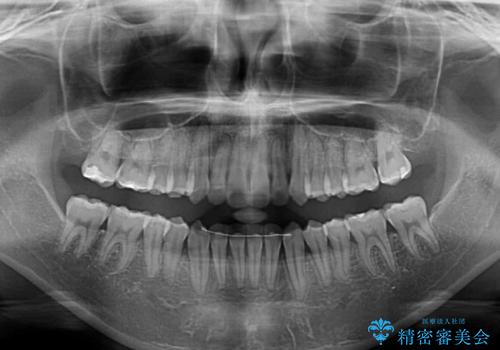

舌側転位している側切歯特有の、切縁の位置が不揃いであったり、根元が内側に引っ込んだ状態であったりという、インビザライン独特の仕上がりになることなく、きれいに整った歯列とすることができました。